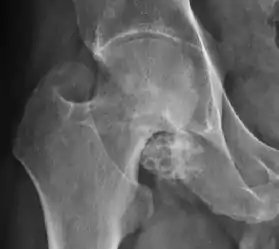

Plain radiography allows us to categorize the hip as normal or dysplastic or with impingement signs (pincer, cam, or a combination of both). Besides these, pathologic processes like osteoarthritis, inflammatory diseases, infection, or tumors can also be identified (Figure 1).[1]

Synovial chondromatosis can be confidently diagnosed by X-ray when calcified cartilaginous chondromas are seen. However, other synovial proliferative processes, such as pigmented villonodular synovitis, require MRI for accurate diagnosis, although noncalcified synovitis can be suspected in radiographs by indirect signs, such as soft tissue swelling and/or erosions in the femoral head, femoral neck, or acetabulum (Figure 7).[1]

X-ray of synovial chondromatosis.[1]

CT of synovial chondromatosis.[1]

In synovial proliferative disorders, MRI demonstrates synovial hypertrophy. In the case of PVNS, characteristic foci of low signal intensity related to hemosiderin deposition are better seen on gradient echo T2* images (Figure 7). In the case of synovial osteochondromatosis, the synovial hypertrophy is accompanied by intermediate signal cartilaginous loose bodies and/or low signal calcified loose bodies.[1]